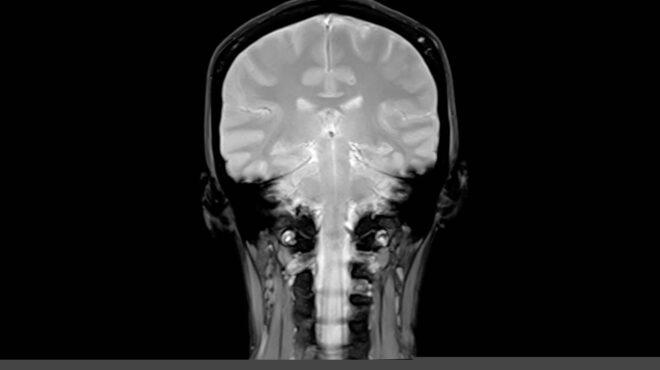

Ο εγκέφαλος που «ξεγελούσε» το Αλτσχάιμερ για 30 χρόνια

Η σπανιότατη περίπτωση μιας Κολομβιανής γυναίκας αποτέλεσε έμπνευση στη μάχη κατά της νόσου και οδήγησε σε ελπιδοφόρα ευρήματα.